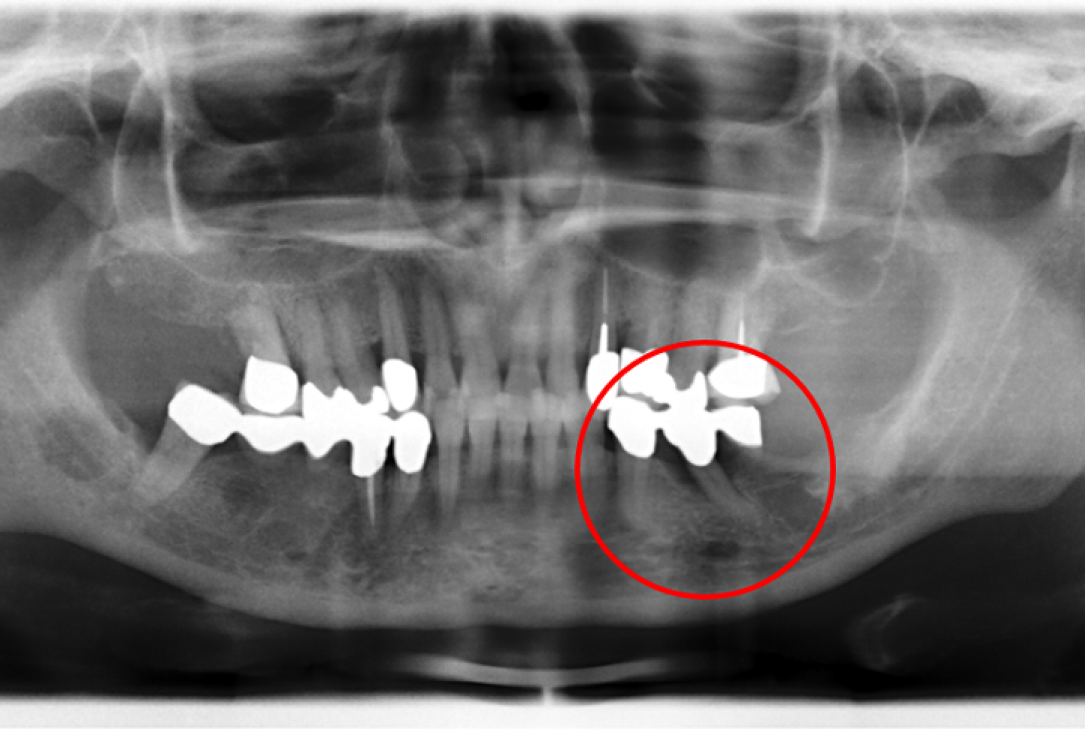

02/02 - Radiographic presentation of the defect 4 years following regenerative periodontal therapy with Straumann® Emdogain®. The radiograph demonstrated a complete defect fill and stable results.

Contained intrabony defect treated using Straumann® Emdogain® - Prof. Dr. Dr. A. Kasaj